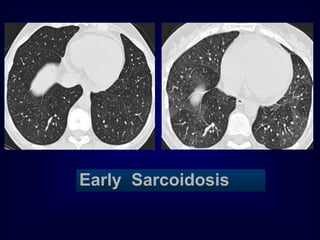

Early Sarcoidosis

Chronic